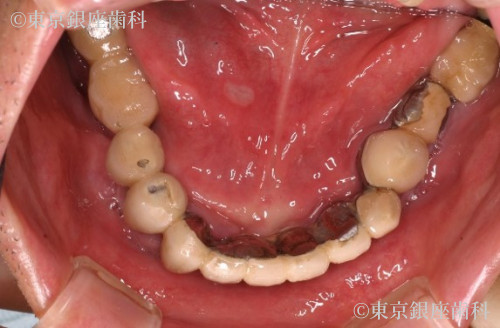

古いタイプのインプラント(ブレードタイプ)を除去し、再度のインプラント手術を経て全顎的な口腔機能回復が得られた患者様

30年前以上に、他院にて下顎に古いタイプのインプラント(ブレードタイプ)での全顎的な口腔機能の回復をしていた。また上顎は入れ歯を装着していた。しかし下顎のブレードタイプインプラントに感染が認められ、インプラントの動揺、周囲の骨に著しい骨吸収が認められ口腔機能の低下が認められた。また下顎管と呼ばれる、下顎の太い血管と神経が入っていいる管の近くまで骨の吸収が進んでいた。咬合に関しても歯の形がすり減り咀嚼が困難な状態となっていた。

ブレードインプラントが下顎管に近接しているので、インプラント除去による下顎の知覚麻痺が生じるリスクを術前のCTの分析で診査し、リスクを避けました。また骨造成は行わず、既存骨(ご本人様の骨)イへのンプラント埋入を行いました。上顎は5本のインプラント、下顎は4本のインプラントを支えとした、上下顎への全顎的な人工歯を装着することで口腔機能の回復が得られた症例となりました。患者様にとても満足の得られることができた症例です